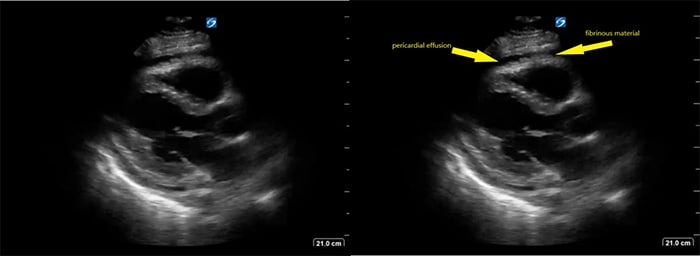

- Pericardial effusion that may or may not contain fibrinous debris: OR = 2.821

Figure 5. Parasternal long axis view of heart with fibrinous pericardial effusion

Video 7. Parasternal long axis view of heart with fibrinous pericardial effusion

-

- In one study of patients with HIV and large pericardial effusions, 69.5% had EPTB as a cause of the effusion.22